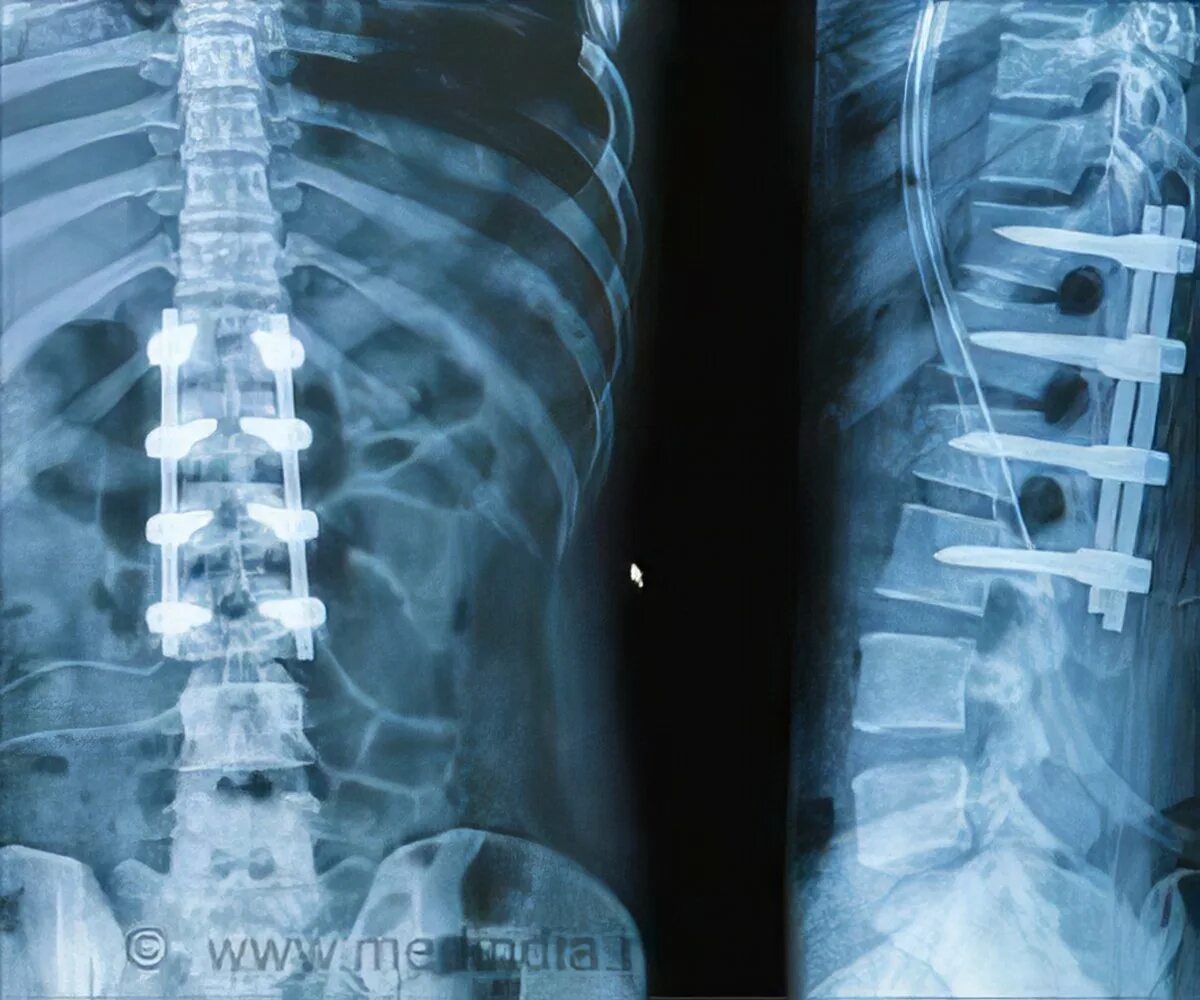

Стабилизирующие операции на позвоночнике